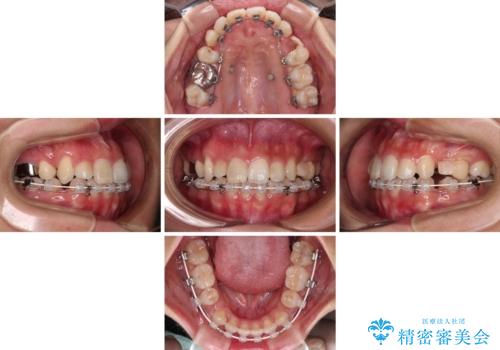

- 矯正装置

- ハーフリンガル

- 2年5ヶ月

- 10-30回